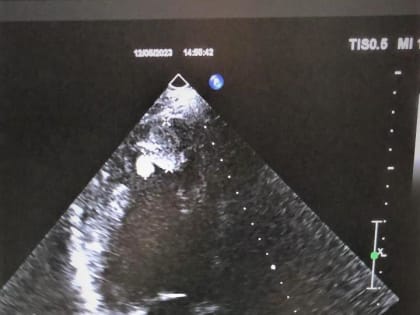

Ростовская область, 17 мая 2023. DON24.RU. В Ростове молодой врач отделения ультразвуковой диагностики горбольницы №6 Татьяна Жукова спасла пациента от вероятной внезапной сердечной смерти.